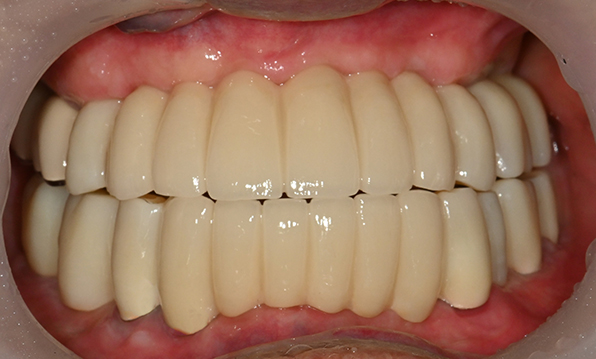

Case 02

Before After